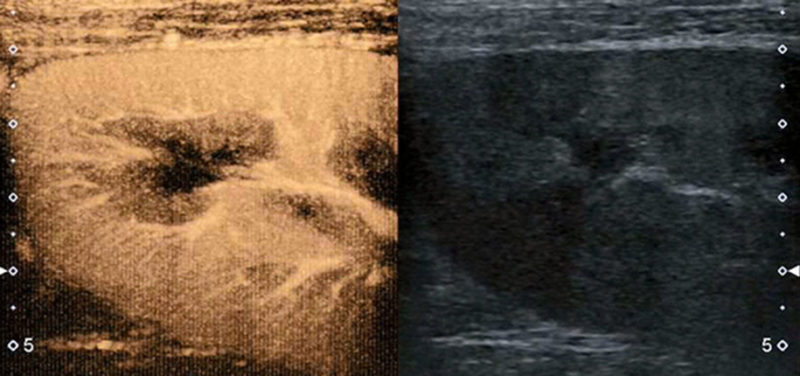

Image: This image demonstrates the blood flow to the upper pole of a kidney. The image on the right is the usual gray-scale ultrasound image of the kidney, whereas the image on the left is contrast-enhanced, showing the vessels and the perfusion of the renal tissue.

Image: This image demonstrates the blood flow to the upper pole of a kidney. The image on the right is the usual gray-scale ultrasound image of the kidney, whereas the image on the left is contrast-enhanced, showing the vessels and the perfusion of the renal tissue.